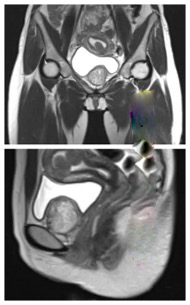

女性的盆腔肿物泌尿外科和妇科均可手术,但男性的盆腔肿物切除均由泌尿外科实施。盆腔肿物可能来源于不同部位或器官,良恶性通常需要术后病理方能确定,后续治疗需要根据病理和分期来决定。手术切除经常是系统治疗的第一步。